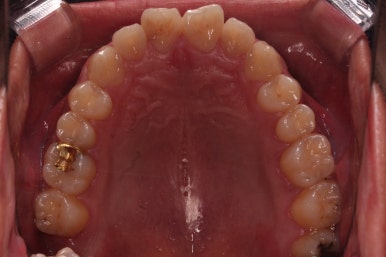

초진 시 입안의 모습입니다.

비교적 고른 편이긴 하나 아랫니가 전반적으로 밀려 나오면서 앞니끼리 부딪혀 있는 양상이고요.

부산교정 장치를 부착했습니다.

이번에 선택하신 장치는 자가결찰 세라믹 장치에요. 스스로 철사를 묶는(결찰) 뚜껑이 달린(자가) 세라믹 성분의 장치인데요.

이번 환자분은 엠파워 클리어라고 하는 장치를 사용했으며 흔히 아신느 클리피씨와 동일한 계열의 장치입니다.